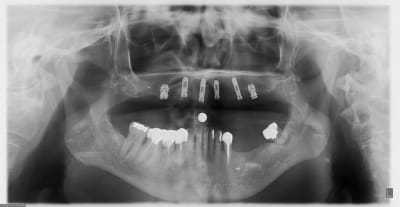

allez, dans ma série, "je remets des sujets" je vous donne quelques nouvelles de ce cas

la raison et vos conseils me sont revenus, j'ai posé hier 2 implants supplémentaires en 17 et 27 (sans les facturer à mon patient)

ce qui me frappe, tout de même, avec les quelques radios prises, c'est la cicatrisation osseuse au niveau de ceux en 15 et 25 (cf panos jour de la pose/3mois/4mois et les "zooms" pose/4mois)

la nature est parfois très sympa...;-)

en 17, non pas dans le sinus...à ras, mais pas dans le sinus